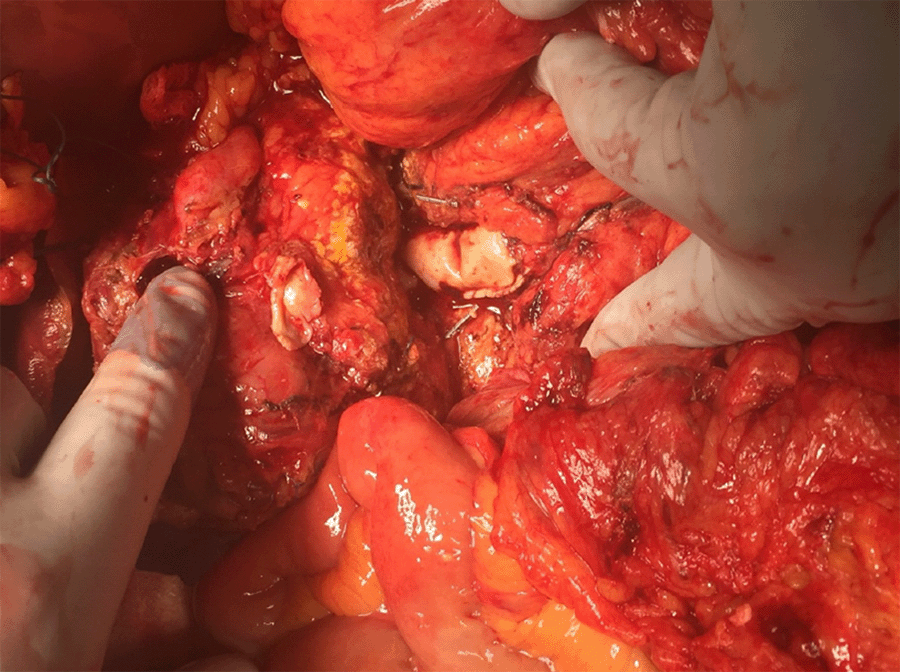

We present a case of a 74-year-old male with no significant past medical history and past surgical history who was initially seen at an outside hospital with abdominal pain and upper gastrointestinal bleeding. A CT of the abdomen and pelvis with contrast reported a giant visceral pseudoaneurysm (>12 cm) of the common hepatic artery a few millimeters after it was taken off from the celiac trunk eroding into the portal vein (PV) (Figure 1). An angiography was done for diagnostic and therapeutic purposes. The angiography showed that the PV had both ante- and retrograde flow. Given the magnitude of the aneurysm, the radiologist at that facility proceeded with coil embolization of the aneurysm but could not control the bleeding. The decision was made to place an endovascular balloon insufflated at the celiac trunk origin to stop the bleeding. He was transferred to our facility for definitive management.

Figure 1. Giant Common Hepatic Artery Aneurysm. Published With Permission